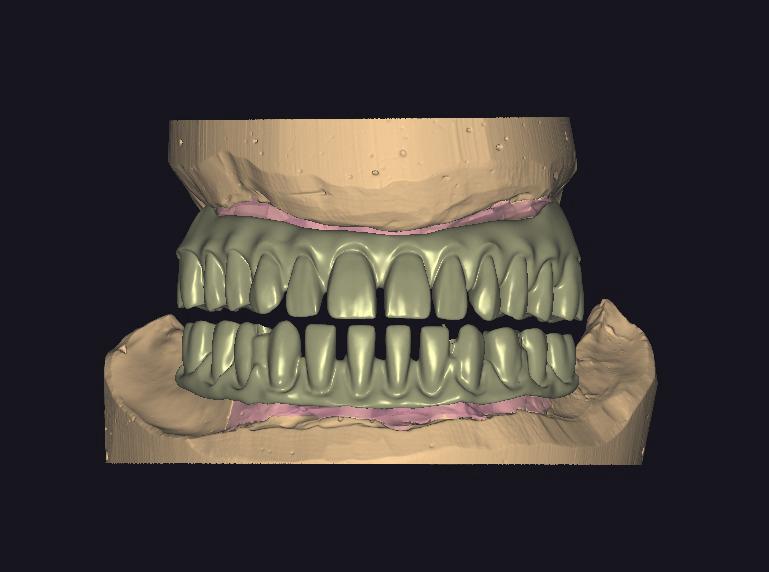

ZIRKONYUM PROTEZLER

ZIRKONYUM

ZIRKONYUM ALT YAPI

IMPLANT USTU ZIRKONYUM

IMPLANT USTU ZIRKONYUM ALT YAPI